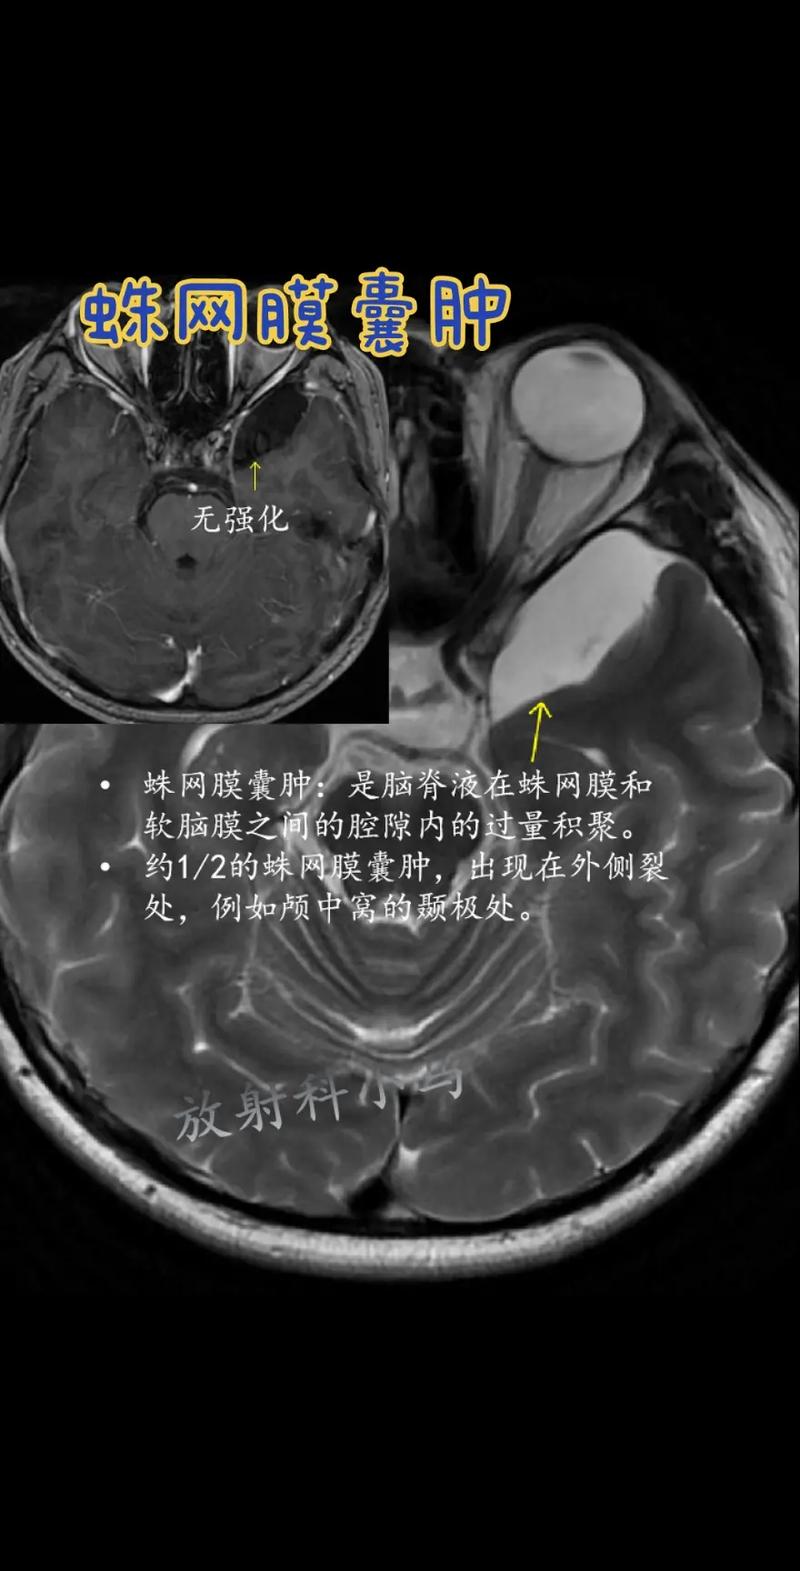

蛛网膜囊肿是脑部或脊髓周围一个充满脑脊液的“水泡”或“囊袋”。

- 囊肿的形成:在某些情况下,蛛网膜会异常分裂,形成一个双层结构,像一个小口袋,这个口袋的壁会不断分泌脑脊液,而分泌出的脑脊液又无法正常流回,越积越多,就形成了囊肿,它本质上是一个良性的、非肿瘤性的结构。

- 中颅窝:这是最常见的位置,通常被称为“外侧裂囊肿”(Sylvian fissure cyst),它位于大脑外侧沟,可能压迫颞叶。

- 磁共振成像:是评估蛛网膜囊肿的“金标准”,它能非常清晰地显示囊肿的大小、位置、形态,以及与周围脑组织、血管和神经的关系,有助于与其他类型的囊肿(如表皮样囊肿)相鉴别。